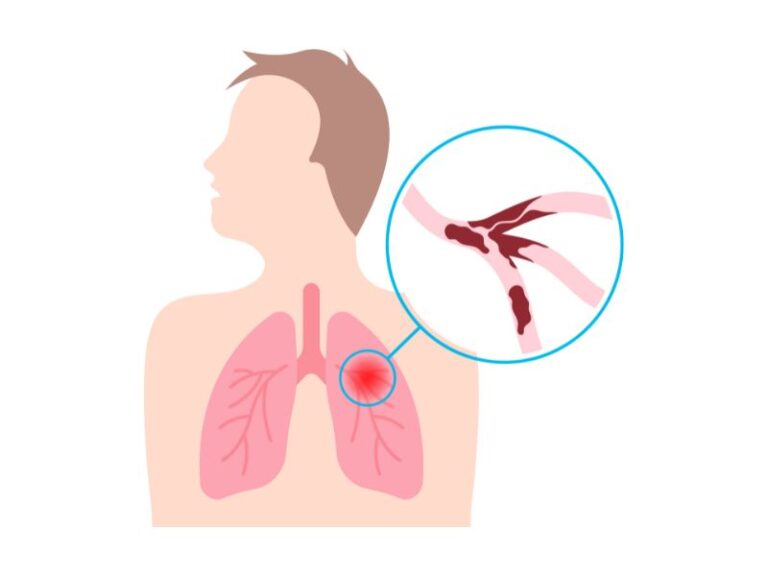

Emfizemul pulmonar nu face parte din categoria bolilor contagioase, însă este frecvent asociat cu bronșita cronică, care se manifestă prin dispnee acută cauzată de diminuarea suprafeţei respiratorii prin distrucția per

Pneumotorax: o afecțiune ce poate pune viața în pericol

Ce este pneumotoraxul?

Pneumotoraxul reprezintă o afecțiune a plămânilor, manifestată prin pătrunderea aerului în cavitatea pleurală, fie prin bronhii, fie prin penetrare exterioară, la nivelul peretelui toracic.

Pleurezie: acumulare lichidiană în cavitatea pleurală

Bolile pleurei sunt caracterizate în principal prin acumulări lichidiene (“apa la plamâni”) și de aer, sau prin prezența de țesut inflamator extins, la nivelul cavității pleurale - pleurezii, pneumotorax și pneumomedia